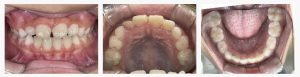

▼After(治療後)

治療終了時には、上下の前歯の咬み合わせが改善し、自然で調和のとれた笑顔になりました。

上あごの成長が促され、口元全体のバランスも整いました。